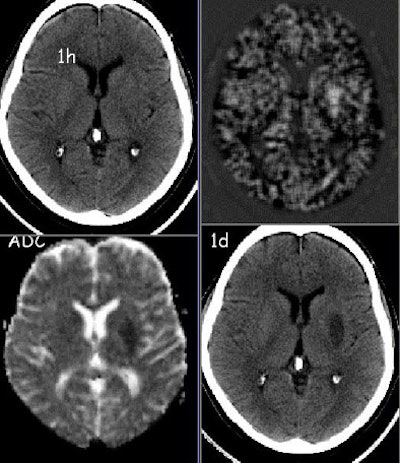

| Clockwise from upper left: 1) CT scan on admission, one hour after onset of dysarthria and hemiparesis. 2) New feature map derived from postprocessing of the original CT scan. 3) Follow-up CT scan the next day shows a hypodense area in the left lenticular nucleus. 4) For comparison, a diffusion-weighted MR image acquired on the day of admission. All images courtesy of Dr. Hans Jürgen Huppertz. |

In all 12 patients, the resulting feature maps showed the areas of infarct much more clearly than in the original CT scans, he said, even eliminating what would have been a false-positive call by the radiologist in one case.